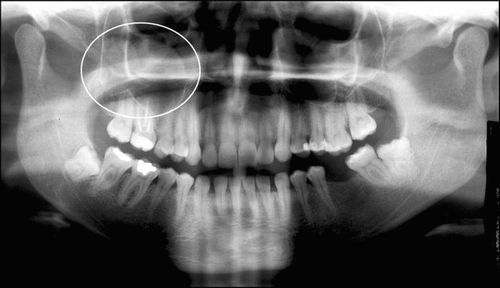

У хворої зоні при пальпації можна виявити характерний для кісти «хрускіт пергаменту». На рентгені освіту на фоні світлої пазухи виглядає як затемнення круглястої форми. Подібними клінічними ознаками характеризуються кісти як лівої, так і правої пазухи.